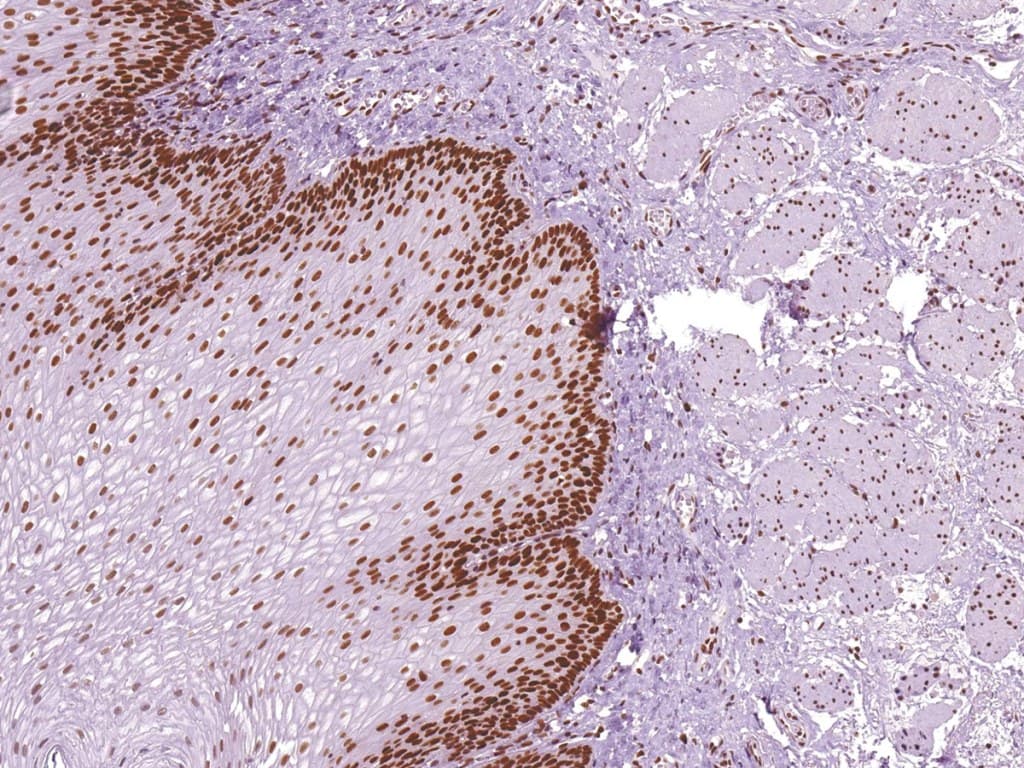

La inmunohistoquímica (IHC) para las proteínas MMR, incluyendo MSH6, es una herramienta validada y esencial para detectar tumores con deficiencia de MMR. La pérdida de la tinción nuclear de MSH6 en las células tumorales, interpretada junto con MLH1, MSH2 y PMS2, indica deficiencia de MMR y puede sugerir síndrome de Lynch o tumores esporádicos con MSI alta.

La IHC de MSH6 se implementa ampliamente en el cribado universal de MMR de los carcinomas colorrectales, identificando a pacientes que podrían no cumplir con los criterios clínicos para las pruebas de cáncer hereditario. Ocasionalmente, la expresión de MSH6 puede ser heterogénea o conservarse a pesar de los defectos funcionales, lo que subraya la importancia de la interpretación experta y la correlación con ensayos moleculares, incluyendo pruebas de MSI o secuenciación de nueva generación, para caracterizar completamente el estado de MMR del tumor.

Los anticuerpos anti-MSH6 diseñados para IHC clínica (con marcado CE/IVD) ofrecen una alta especificidad y reproducibilidad en tejido fijado en formalina e incluido en parafina (FFPE). Permiten una distinción precisa entre la expresión conservada en células estromales o inflamatorias normales (controles internos) y la pérdida en los núcleos tumorales.